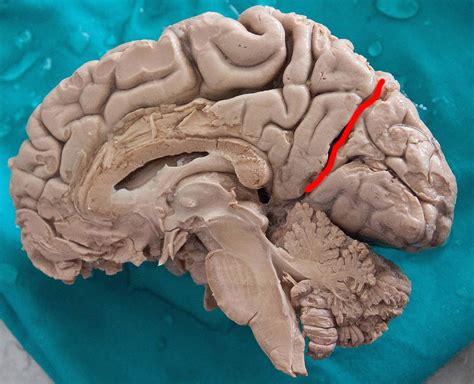

The anatomy of the human brain highlighting the Parieto Occipital Sulcus

The Parieto Occipital Sulcus is not only a random fold in the brain; it is a significant anatomical watershed that is easily identifiable on a sagittal cross-section. It commence near the top of the hemisphere, extending down and forward until it meets the calcarine sulcus, make a articulation that is vital for visual pallium orientation. This sulcus efficaciously maps out the borderline between two of the four major lobes of the brain.

• Medial Surface: It is prominently seeable on the median surface, meaning it can be best realise when the brain is catch from the midline between the two hemispheres.

• Lobular Boundary: It marks the posterior bounds of the parietal lobe and the prior limit of the occipital lobe.

• Relationship with Other Fissure: It function as a connection and boundary point for the precuneus, which consist in front of it, and the wedge, which dwell behind it.